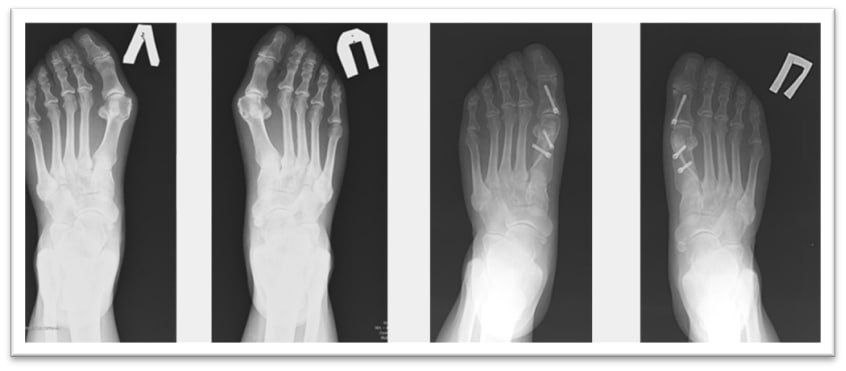

-Высокотехнологичные фиксирующие элементы не требуют удаления и не доставляют неудобств в дальнейшем. Они не мешают таким исследованиям, как МРТ, на них не реагируют рамки досмотра и металлоискатели. Имеющаяся линейка винтов позволяет выполнять фиксацию при самых сложных деформациях. Причем, даже пожилым женщинам с хрупкими, пораженными остеопорозом костями. Например, недавно мы успешно избавили от запущенной проблемы 76-летнюю пациентку. Ей провели 11 корригирующих остеотомий в ходе одной операции. Такой большой объём вмешательства обусловлен деформацией всех пальцев стопы и необходимостью вернуть каждый в правильное анатомическое положение, - объясняет заведующий отделением травматологии и ортопедии №1 Сергей Глиняный.